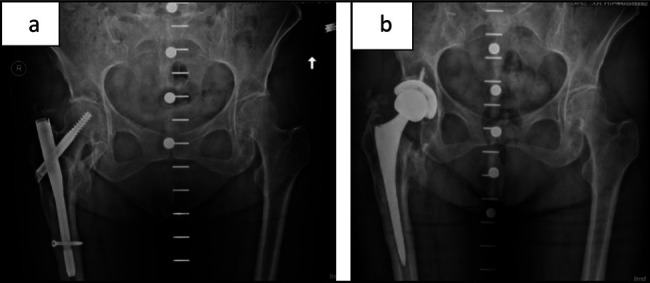

Results: A diaphyseal-engaging revision stem was used in 13 cases, with metaphyseal press-fit stems and cemented stems each used in 3 cases. Two patients (one diaphyseal stem, one cemented stem) sustained intraoperative greater trochanteric fractures. No postoperative fractures were found. Four emergency department visits (21%) and one unplanned readmission (5%) were reported within 30 days, with 1 emergency department visit (5%) and two readmissions (11%) within 90 days. Stratified by stem type, we observed no notable difference in length of stay or procedure length.

Discussion: This is the first study to investigate conversion to THA from short IMN. Overall, there were two intraoperative fractures, but no distal fractures or revisions. Although the distal interlock screw was commonly bypassed with a revision-type diaphyseal stem, this was not universal. Further research is needed to determine if primary arthroplasty stem designs can be used in this setting.